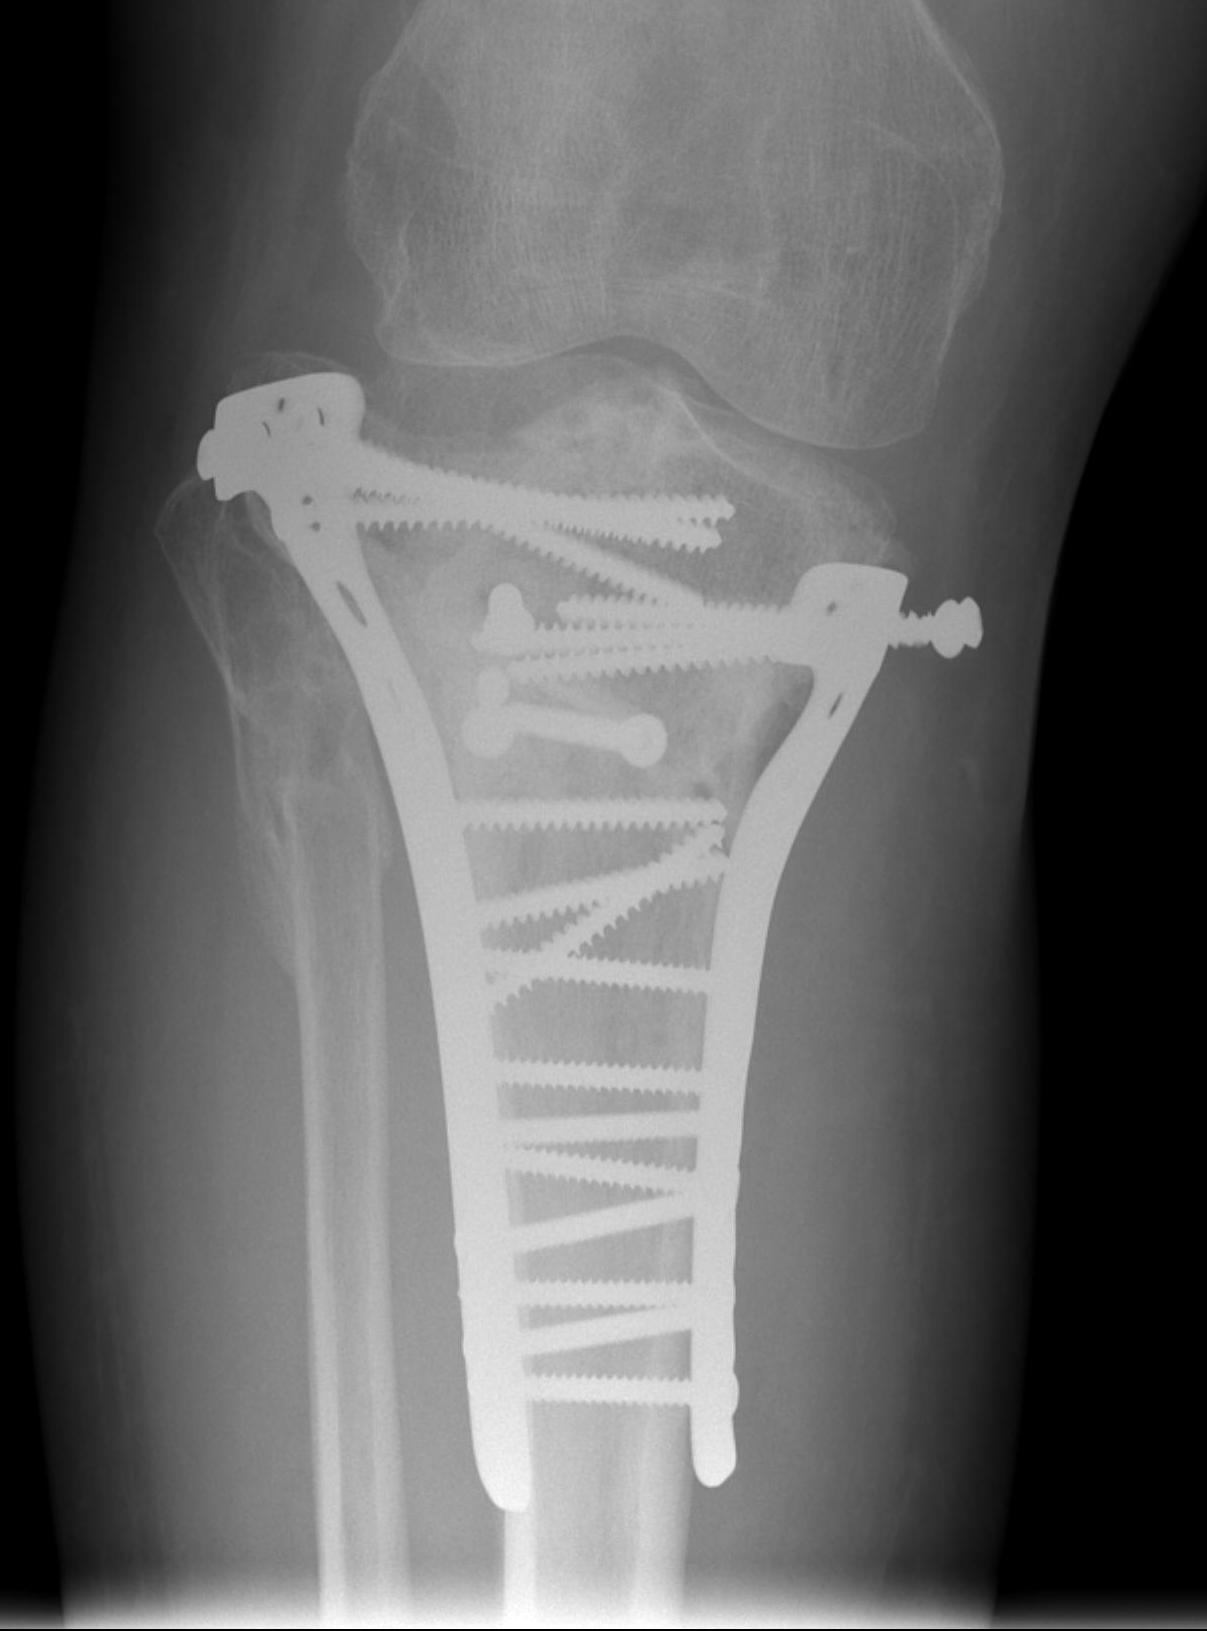

Type V Bicondylar

Options

1. Medial and Lateral plating

Technique

- depends on which of the three columns affected

- anterolateral approach for lateral column

- posteromedial appraoch for medial / posterior column